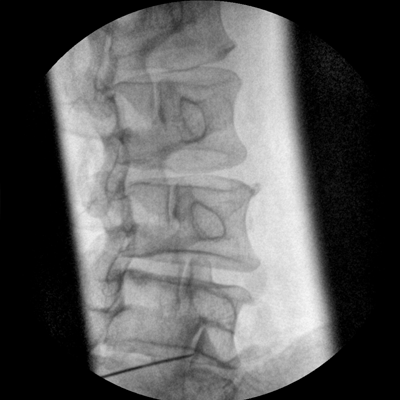

專(zhuān)業(yè)的圖像處理系統(tǒng),為您提供高分辨率、高灰階圖像。